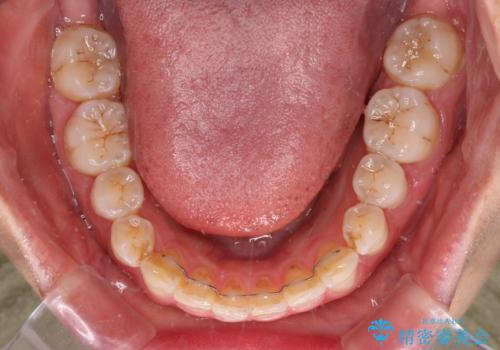

前歯の捻れを改善 インビザラインによる矯正治療

- 前歯の翼状捻転を気にして来院された患者様です。

全体的に叢生は軽度であったため、インビザラインにて矯正治療を行うこととしました。

前歯の幅の大きさも気になっていたため、IPRにより叢生を解消するとともに、歯の大きさも改善しました。